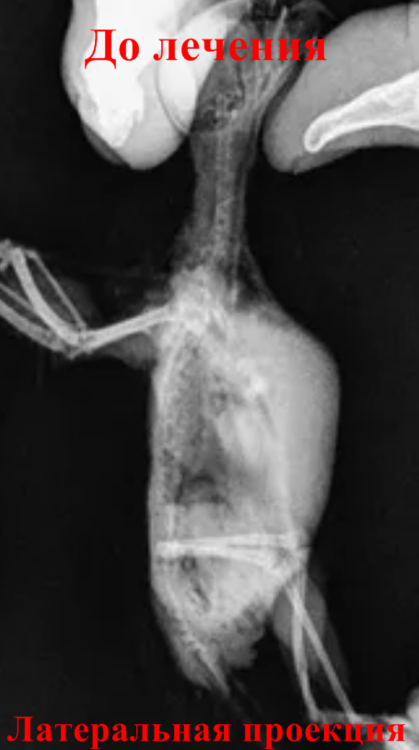

Сделал рентген. На соседнем форуме откликнулась Зося (за что огромное ей спасибо): "Сильно увеличены семенники. Но производят впечатление просто воспаленных (неинфекционное воспаление)."

Латеральная проекция.png